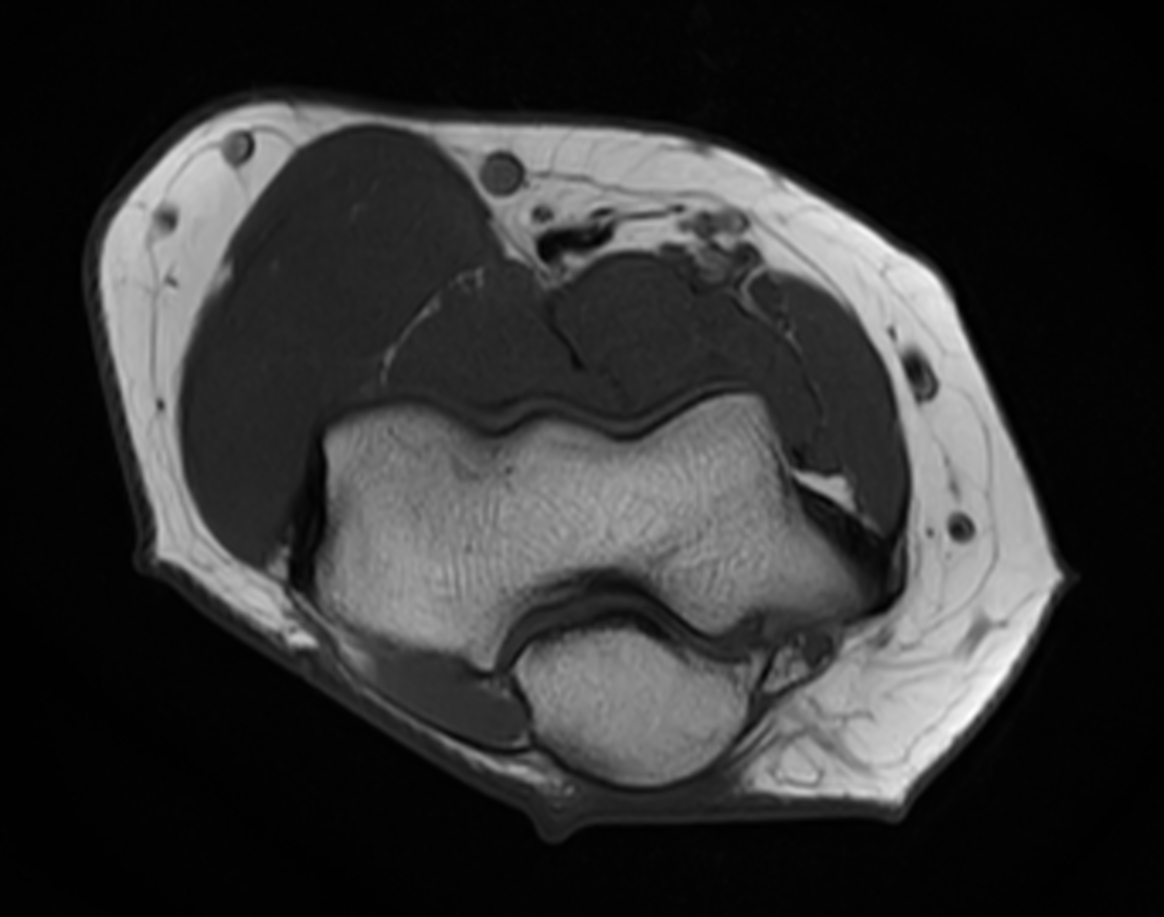

Axial T1w SPAIR